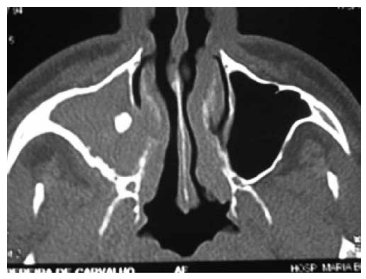

Paciente com obstrução nasal e rinorreia purulenta há 4 meses realiza a tomografia computadorizada (TC) a seguir. Assinale a alternativa correta com relação à principal hipótese diagnóstica.